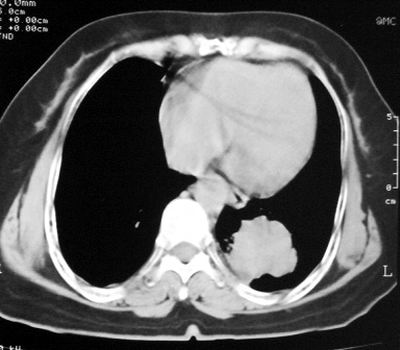

患者,女,64岁,4年前左腮腺"多形性"腺瘤手术治疗史.现复查胸部ct见左下肺块状影,该影与原左腮腺手术是否有联系?

本次复查胸部ct

左下肺软组织块影,有分叶、毛刺、空泡及胸膜牵拉征,左下肺周围性肺癌。

左肺下叶周围型肺癌,支持!(软组织肿块+分叶+毛刺+空泡+胸膜凹陷征)

左下肺软组织密度影,可见分叶,边缘可见毛刺征,胸膜增厚,强烈要求左下肺周围型肺癌

左下肺后基底段实性肿块,周围有毛刺,病变周围有肺气肿,与降主动脉间有条带状影相连,病灶4年前查体发现,纵隔内未见肿大淋巴结。考虑.肺隔离症,建议增强扫描与周围型肺癌鉴别。